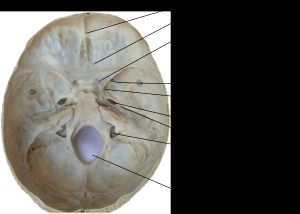

두개골 내면 바닥의 구멍을 표시한 이미지

원형구멍은 두개골의 구멍 중 하나로, 나비뼈의 앞쪽 및 안쪽에 위치하며 위턱신경(V2)이 지나가는 통로이다. 태아기부터 성장하며, 출생 시 약 2.5mm에서 성인기에는 평균 3.55mm의 직경을 갖는다. 원형구멍은 삼차신경의 가지인 위턱신경 외에도 원형구멍동맥과 이끌정맥이 통과하며, 라틴어 'forare'에서 유래된 용어이다.

원형구멍은 나비뼈의 앞쪽과 안쪽에 위치하는 구멍 중 하나로, 두개저를 구성하는 구조물이다. 상악 신경은 이 원형구멍과 익구개와를 통해 두개골 밖으로 나간다.

원형구멍은 삼차신경의 두 번째 가지인 위턱신경(V2, 상악 신경)이 지나가는 통로 역할을 한다.[11][4] 상악 신경은 두개저에 위치한 원형구멍과 익구개와를 거쳐 두개골 밖으로 나간다. 또한, 원형구멍으로는 원형구멍동맥과 이끌정맥(교통 정맥)도 통과한다.[11][4]